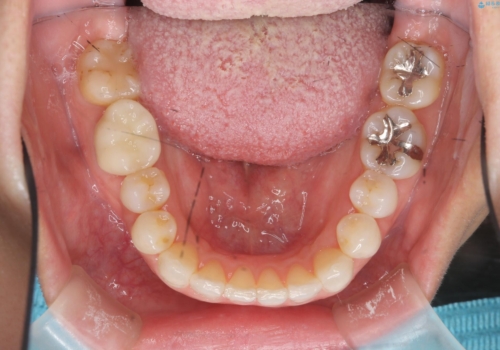

30代女性 前歯のがたつき

- 前歯のがたつきを主訴に来院。

右下の奥の銀歯も治療しています。

- 115.5万円 矯正治療 85万円、奥歯ジルコニアクラウン11万円(ZrCr 10万円、仮歯1万円、矯正用仮歯2万円)セラミックインレー7万円費用は治療当時の料金となります

下の前歯を下げるため、IPR(歯をわずかに削る処置)を行っています。